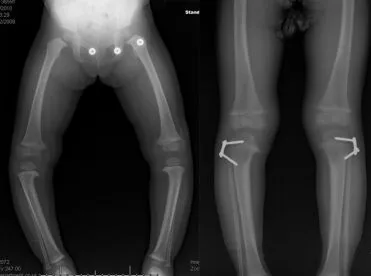

Paley 研究院创立的 3D 解剖重建与个性化矫形计划(Paley’s Planning System)通过三维建模、多平面畸形分析、虚拟手术模拟与个性化器械配置,为复杂肢体畸形、先天骨骼异常和骨不连病例提供科学、安全、可预测的矫形方案,是全球骨科重建领域的金标准。